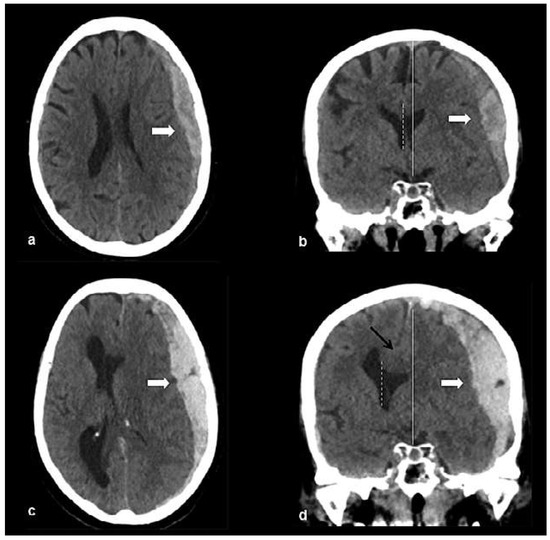

Head and brain trauma: general aspects and neuroimaging

by Johanna Maria Lieb, Christoph Stippich and Meritxell Garcia

Swiss Arch. Neurol. Psychiatry Psychother. 2015, 166(8), 279-292; https://doi.org/10.4414/sanp.2015.00374 - 1 Jan 2015

In this article the general clinical aspects, imaging indications and different injury mechanisms of traumatic brain injury (TBI) are reviewed. In addition, the different imaging modalities and strategies are presented, including more specific imaging features of the various injuries. Computed tomography (CT) is [...] Read more.

In this article the general clinical aspects, imaging indications and different injury mechanisms of traumatic brain injury (TBI) are reviewed. In addition, the different imaging modalities and strategies are presented, including more specific imaging features of the various injuries. Computed tomography (CT) is the imaging modality of choice in the acute phase owing to its wide availability and short scanning time, as well as to its high sensitivity for the detection of fractures and acute bleeding. Although magnetic resonance imaging (MRI) is superior to CT in many other aspects, it plays no role in the acute phase. MRI, however, has been proven to be useful and complementary to CT in the subacute and chronic stages as well as in the case of inconclusive results on initial CT. Especially the use of standard sequences like fluid attenuated inversion recovery (FLAIR), diffusion and susceptibility weighted imaging (DWI and SWI) have been shown to increase the diagnostic potency in diffuse axonal injury, in mild brain trauma and also in more chronic stages of TBI. The use of more advanced MRI techniques such as diffusion tensor imaging (DTI), magnetic resonance spectroscopy (MRS), functional MRI (fMRI) and magnetic transfer imaging (MTI) can further complete the diagnostic evaluation and give insights into different pathophysiological processes in TBI. Full article